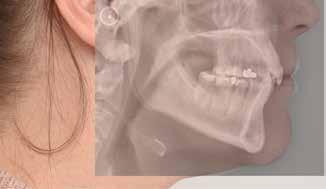

Røntgenanalyse viser fravær af -6 samt et velholdt tandsæt uden tegn på sygdom. Profilrøntgenbilledet viser et skeletalt

dybt bid, men normal inklination af fortænder i over- og underkæbe (Fig. 1B).